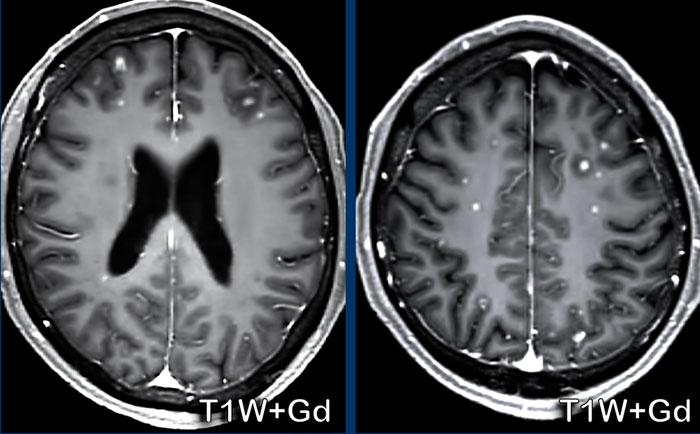

U lympho

Các hình ảnh này của bệnh nhân 63 tuổi.

Hình ảnh

CT cho thấy tổn thương tăng tỷ trọng quanh não thất kèm phù não xung quanh.

Trên chuỗi xung T2W, tổn thương có tỷ trọng tương đối thấp. Tổn thương ngấm thuốc đồng nhất với nhiều tổn thương ngấm thuốc quanh não thất.

Tỷ trọng trên CT và phân bố tổn thương gợi ý mạnh đến u lympho.

GBM lan rộng dưới màng nội tủy

Bệnh nhân này đã được điều trị GBM trước đó và hiện tái phát tại thùy trán trái.

Có ngấm thuốc dày dọc theo não thất bên trái, biểu hiện của sự lan rộng khối u theo đường dưới màng nội tủy.